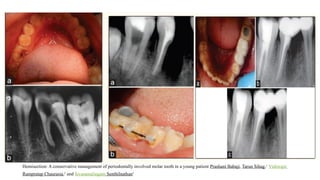

Hemisection: A conservative management of periodontally involved molar tooth in a young patient Prashant Babaji, Tarun Sihag,1

Vishwajit

Rampratap Chaurasia,2

and Sivaramalingam Senthilnathan3